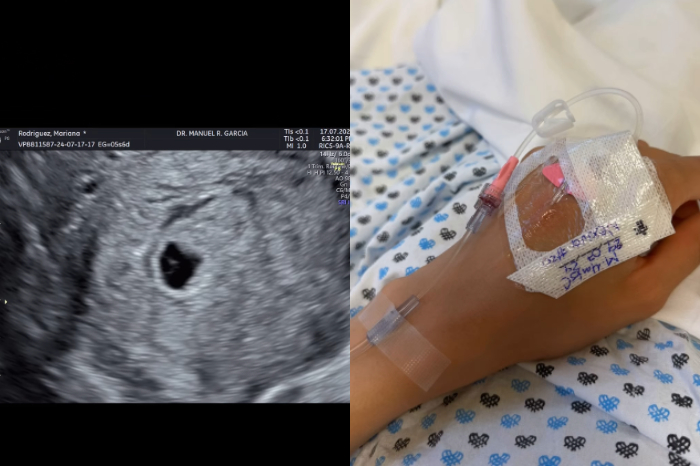

La influencer publicó un video que muestra el momento en el que se enteró que estaba embarazada, seguido de uno donde se encontraba en el hospital debido a un aborto espontáneo.

La influencer publicó un video que muestra el momento en el que se enteró que estaba embarazada, seguido de uno donde se encontraba en el hospital debido a un aborto espontáneo. "Duele como si fuera la primera vez, tengo 5 angelitos en el cielo", agregó la excandidata a la alcaldía de Monterrey.

Horas después de haber publicado el conmovedor video, reapareció en sus redes sociales para sincerarse sobre el doloroso momento que se encuentra atravesando. "Han sido días difíciles emocionalmente, de repente estoy muy bien, de repente lloro, físicamente también cuesta, me hicieron una aspiración el día lunes. Este embarazo nos vino a tomar de sorpresa de forma natural, yo pensé que era mi recompensa por cómo se habían dado las cosas antes de Mariel pero la vida tiene otros planes", reveló.